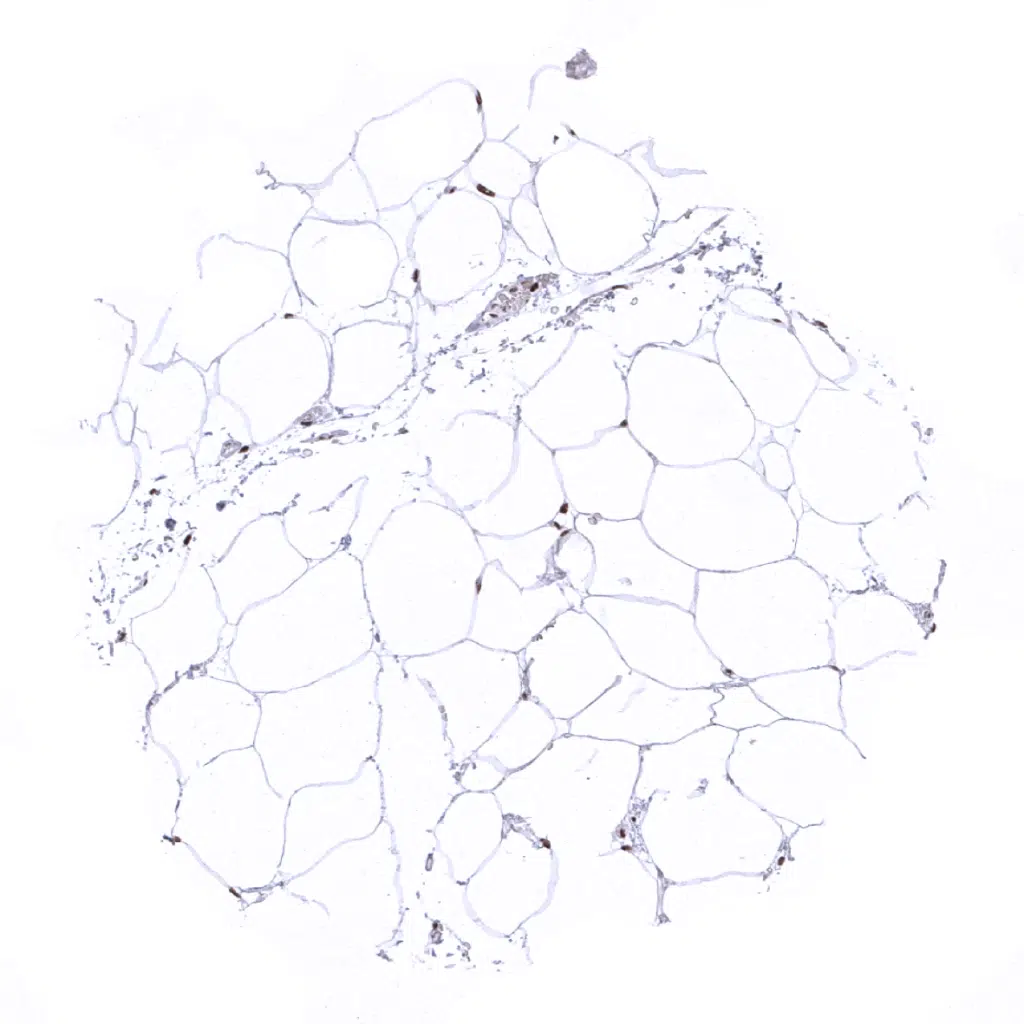

Fat